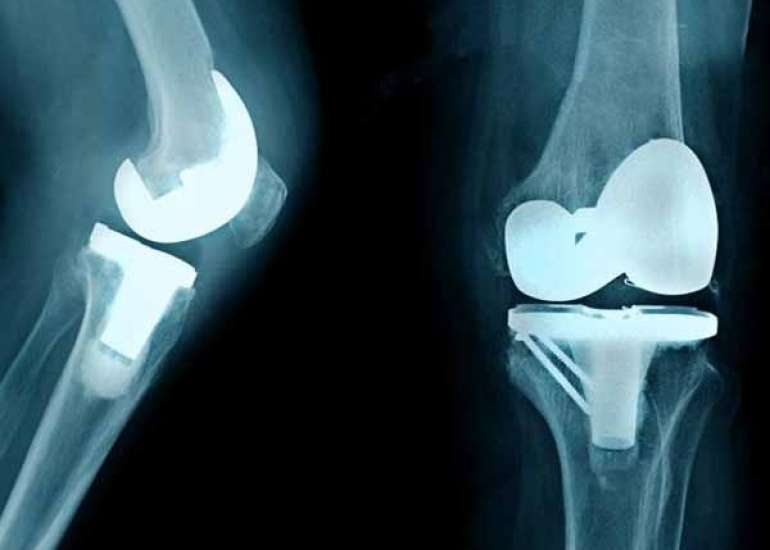

Director (Orthopaedics & Joint Replacement) & Head of Unit-1, Max Smart Super Speciality Hospital, Saket